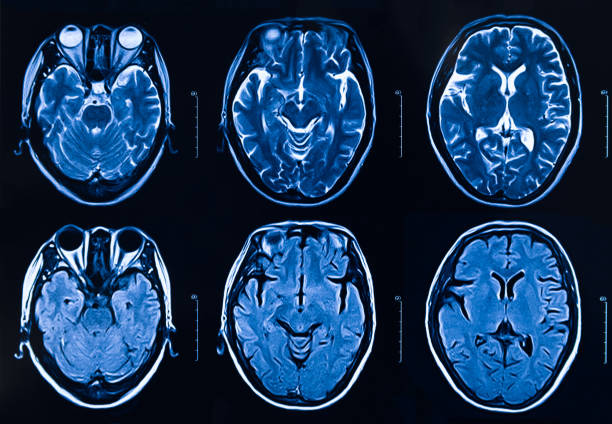

本研究納入2018年1月1日至2020年10月31日發(fā)病168小時內(nèi)發(fā)生急性ICH的患者。間充質(zhì)干細胞被靜脈注射給9名患者(5名女性,4名男性),平均年齡(范圍)為61(36-84)歲。表1總結(jié)了人口統(tǒng)計學和臨床??特征 。出于描述目的,患者按照入組順序獲得編號,并連續(xù)分配到三組中的一組,每組三人。根據(jù)模型 2 分割,ICH體積范圍為0.1至54.9mL(平均ICH體積為23.5mL)。5例ICH累及局部腦葉,其余則位于基底節(jié)或外囊深處。在三名患者中,ICH位于丘腦(圖1),在一名患者中,血腫位于多個腦結(jié)構(gòu)(即尾狀核、殼核和蒼白球)。平均而言,MSC在ICH后3天進行注射。